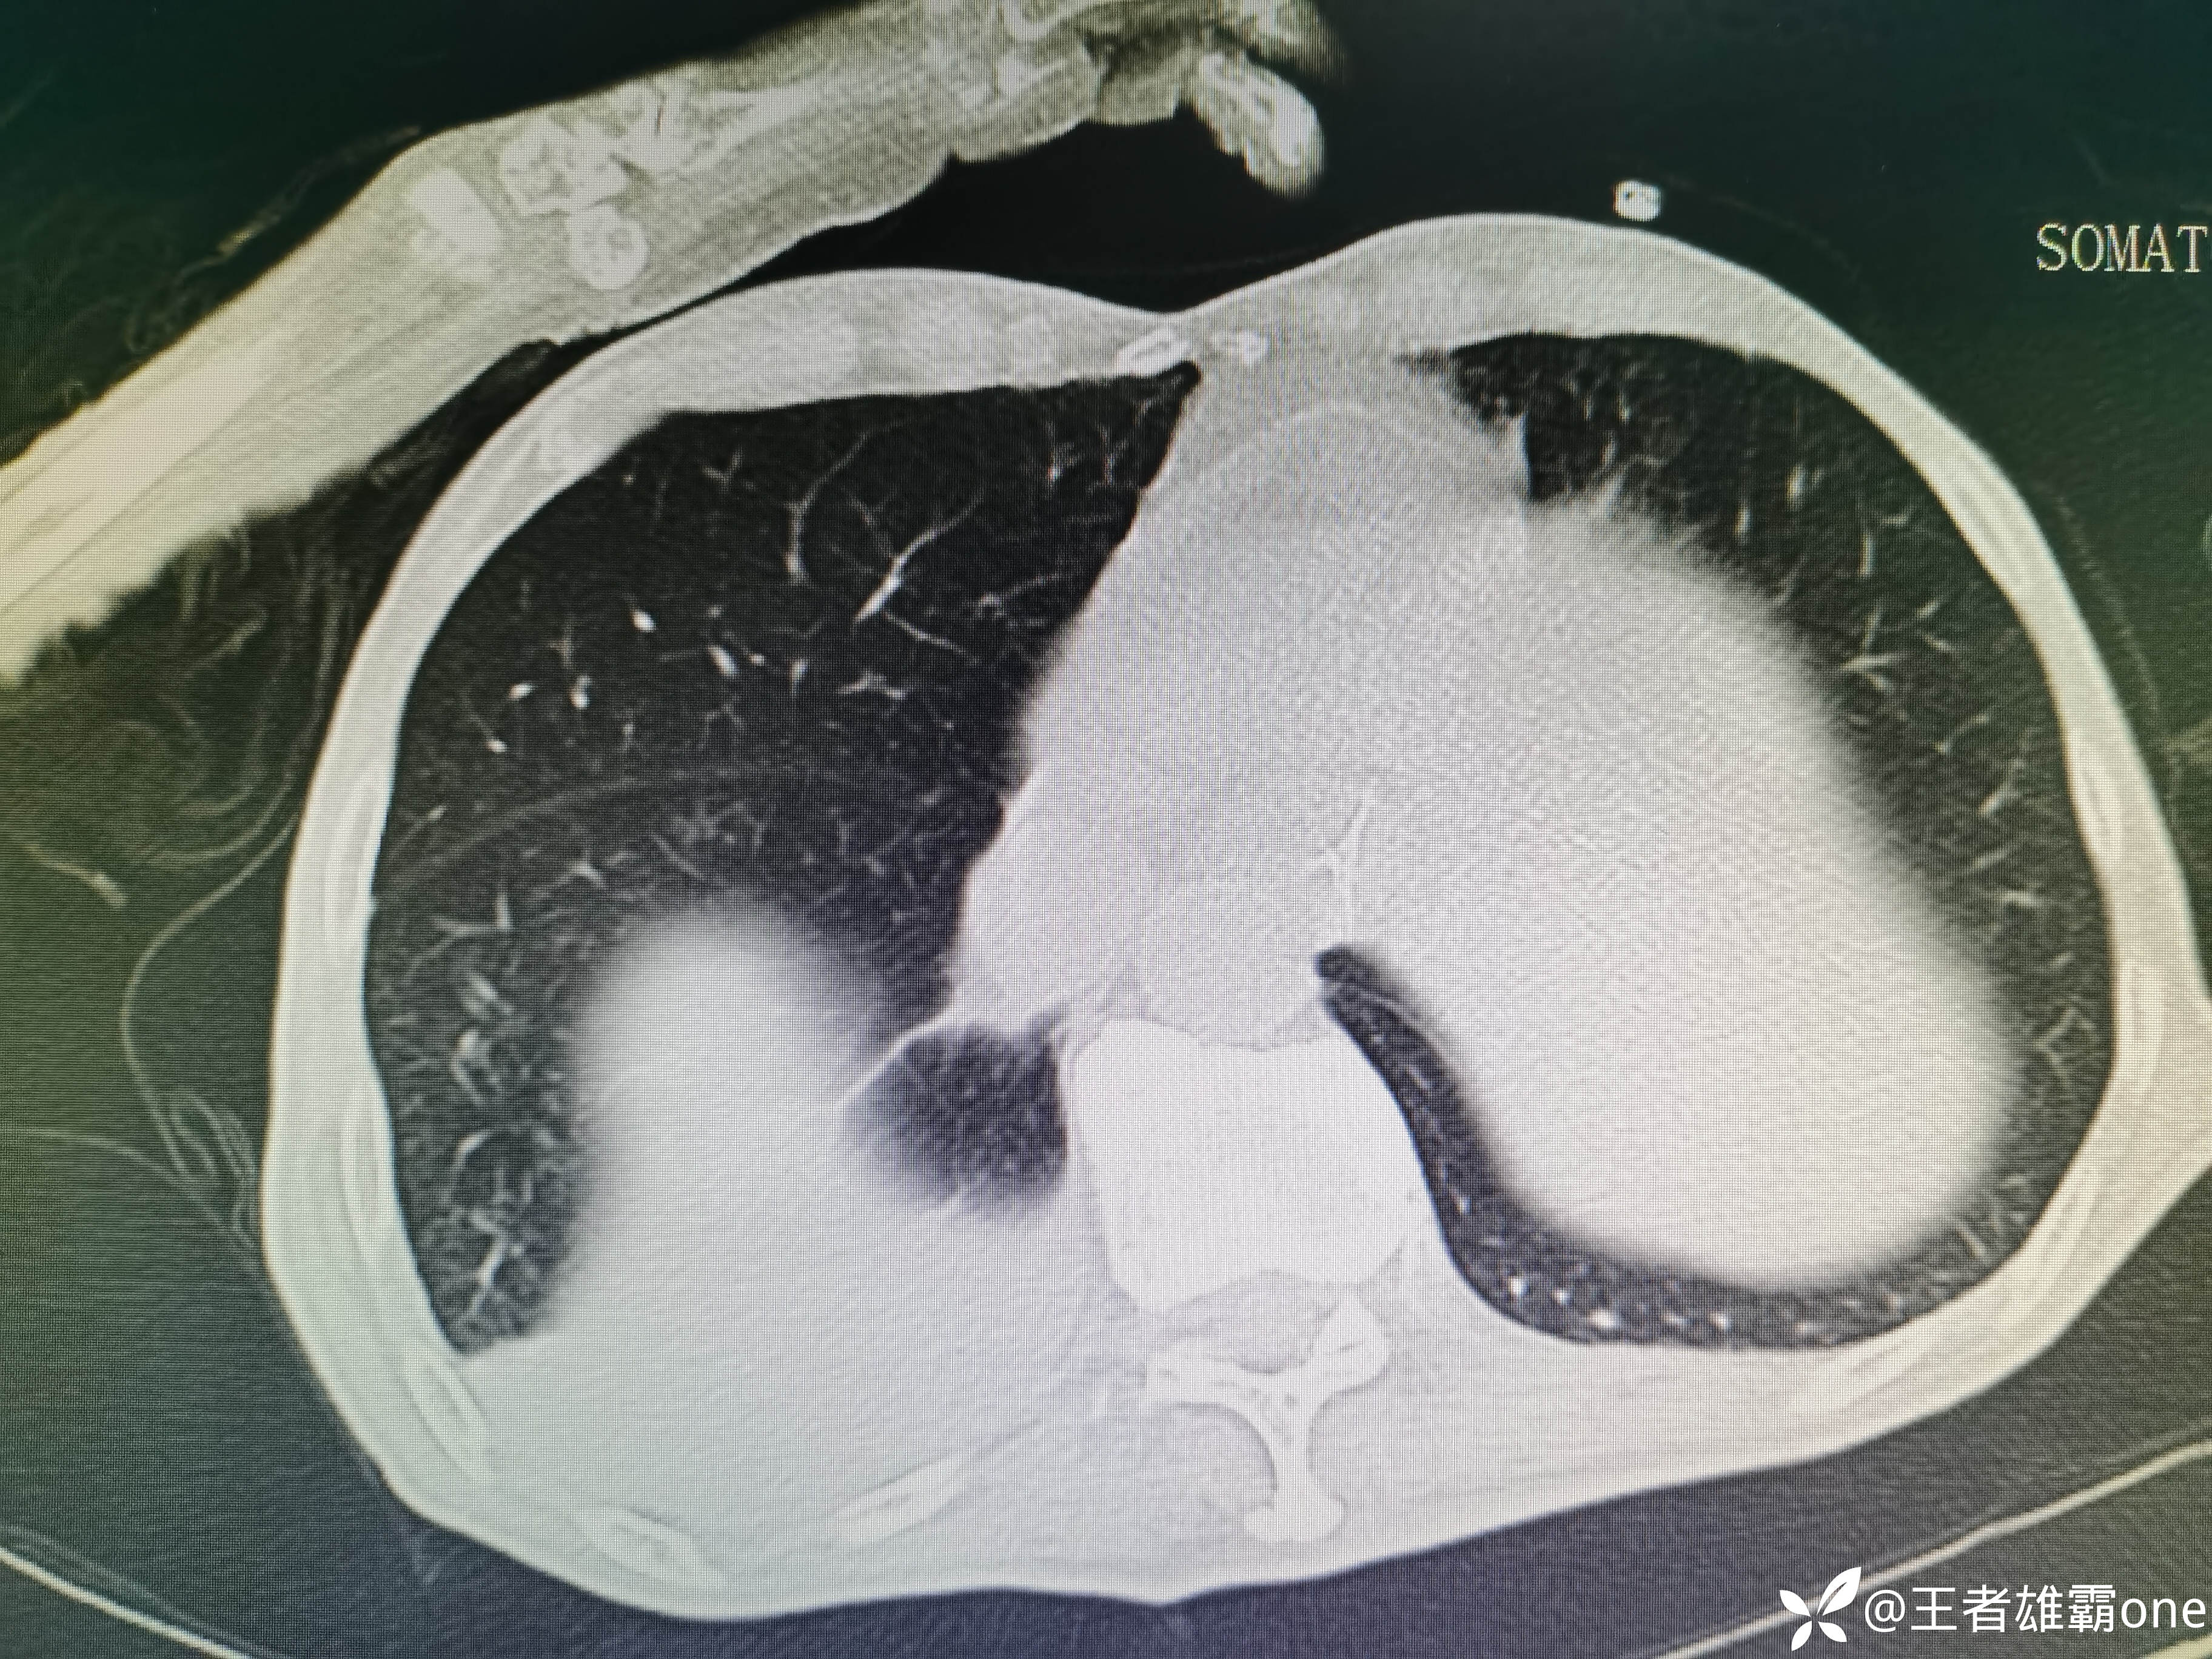

入院时胸部CT:

具体图片: